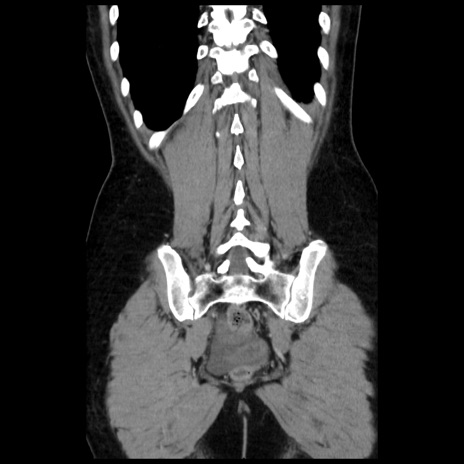

症例10(冠状断像)

症例